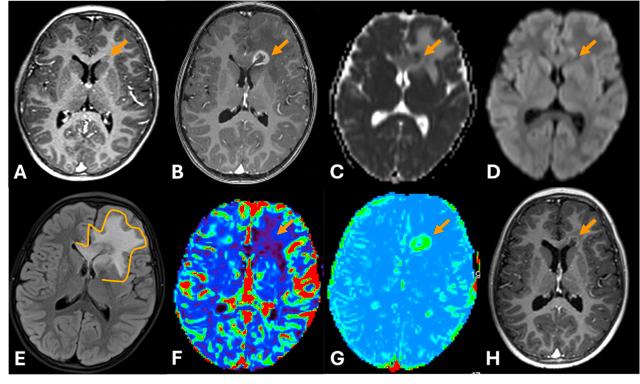

Un nouveau modèle d’IA analyse des IRM cérébrales en quelques secondes

Des chercheurs de l'université du Michigan ont développé un système d'intelligence artificielle capable d'interpréter des IRM cérébrales en quelques secondes et d'identifier les pathologies neurologiques. Ce ...